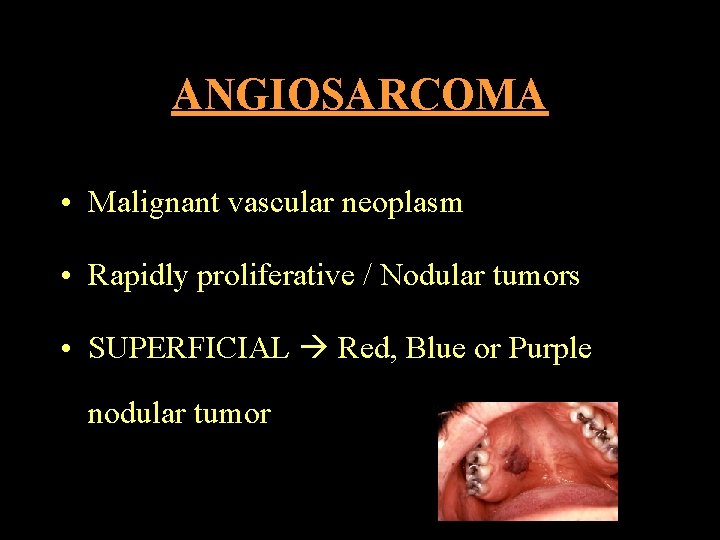

ANGIOSARCOMA • Malignant vascular neoplasm • Rapidly proliferative / Nodular tumors • SUPERFICIAL Red, Blue or Purple nodular tumor